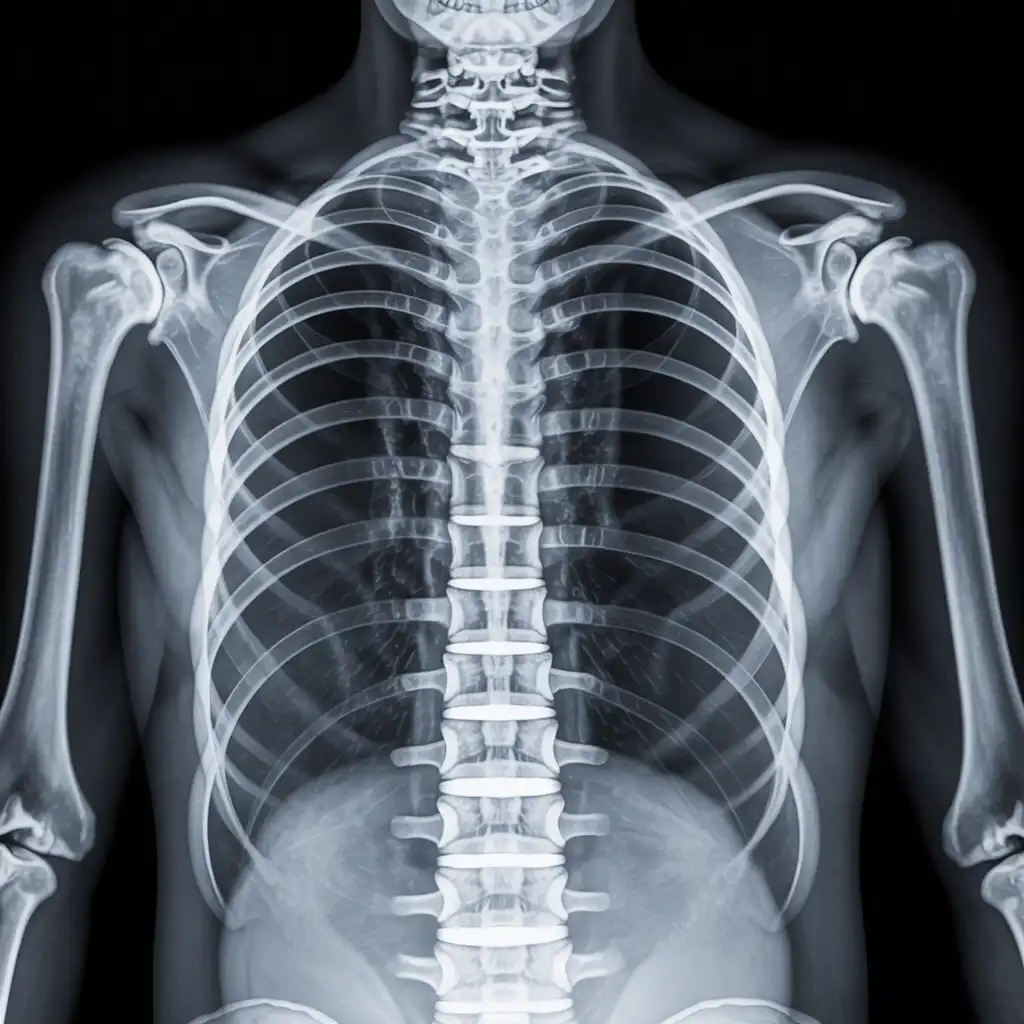

Da anni offriamo un servizio di radiografie a domicilio pensato per garantire ai nostri pazienti la stessa qualità diagnostica degli esami eseguiti in ospedale, ma con la comodità e la sicurezza della propria casa.

Abbiamo effettuato migliaia di esami direttamente presso abitazioni, residenze e strutture assistenziali, utilizzando apparecchiature digitali portatili certificate e procedure rapide e sicure.